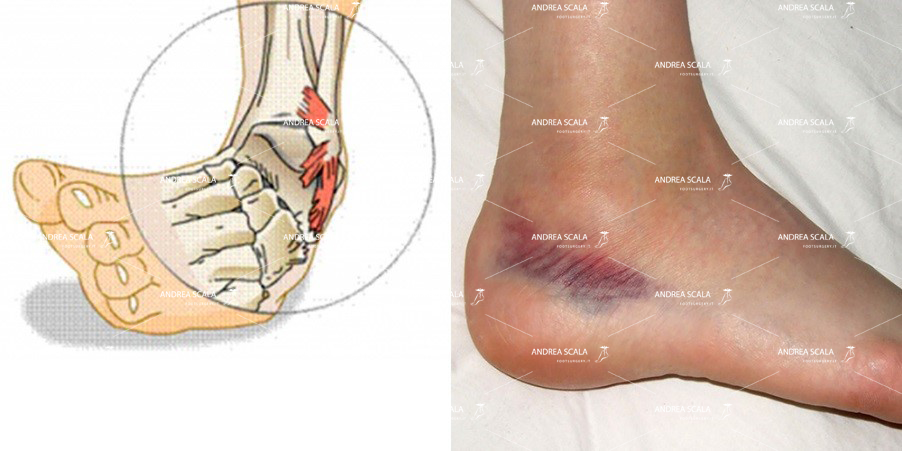

Meccanismo di lesione

Il meccanismo che porta a questo infortunio può esser di natura traumatica, specie negli sport da contatto, o anche solamente da atterraggio o appoggio sbagliato al suolo. Il movimento della caviglia si può riassumere in una eccessiva flessione plantare e adduzione o una inversione eccessiva, a cui i nostri sistemi di difesa non riescono ad opporre adeguata resistenza.

I sintomi più comuni sono dolore, edema e/o ematoma, impotenza funzionale ed instabilità.